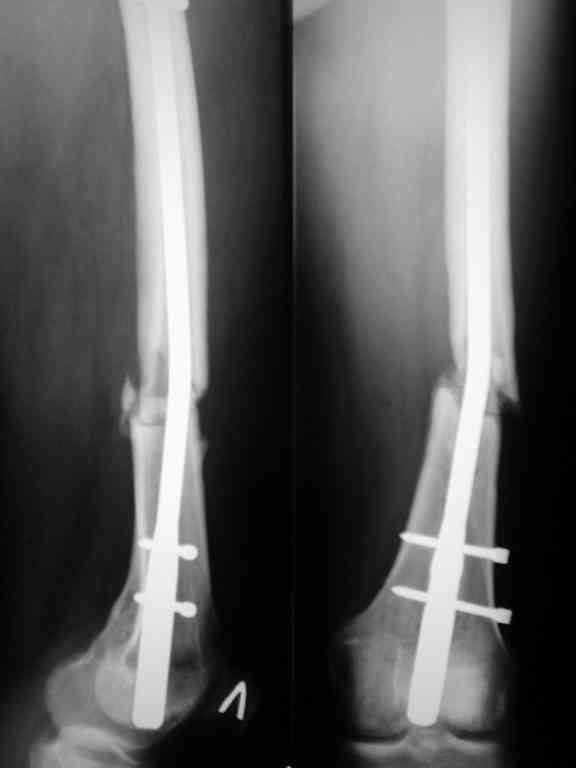

При первичном интрамедуллярном остеосинтезе применялся блокируемый гвоздь диаметром 9 мм ретроградно. У пациентки узкий костномозговой канал, поэтому были сложности (рассверливали долговато). Что касается разреза то его длина была 3-4 см не более. Т.е. насчет девитализации я согласен, но именно за счет рассверливания.

Винты с внутренней стороны кости фиксируют трансплантат, взятый из гребня подвздошной кости. Он довольно массивный и был уложен в дефект по передне-медиальной поверхности кости. тут уж пришлось действительно открываться на совесть.

В приложении рентгенограмма бедра за авгутст 2005 с согнутым гвоздем и первичные.